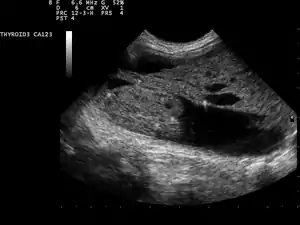

Ultrasound artifacts showing a "comet tail" from a colloid nodule indicate a benign nodule

Ultrasound imaging is useful as the first-line, non-invasive investigation in determining the size, texture, position, and vascularity of a nodule, accessing lymph nodes metastasis in the neck, and for guiding fine needle aspiration cytology (FNAC) or biopsy. Ultrasonographic findings will also guide the indication to biopsy and the long term follow-up.[10] High frequency transducer (7–12 MHz) is used to scan the thyroid nodule, while taking cross-sectional and longitudinal sections during scan. Suspicious findings in a nodule are hypoechoic, ill-defined margins, absence of peripheral halo or irregular margin, fine, punctate microcalcifications, presence of solid nodule, high levels of irregular blood flow within the nodule[11] or "taller-than-wide sign" (anterior-posterior diameter is greater than transverse diameter of a nodule). Features of benign lesion are: hyperechoic, having coarse, dysmorphic or curvilinear calcifications, comet tail artifact (reflection of a highly calcified object), absence of blood flow in the nodule, and presence of cystic (fluid-filled) nodule. However, the presence of solitary or multiple nodules is not a good predictor of malignancy. Malignancy is only diagnosed when ultrasound findings and FNAC report are suggestive of malignancy.[11] The TI-RADS (Thyroid Imaging Reporting and Data Systems) are sonographic classification systems which describe the suspicious findings of thyroid nodules.[12] It was first proposed by Horvath et al.,[13] based on the BI-RADS (Breast Imaging Reporting and Data System) concept. Several systems were subsequently proposed and adopted by international scientific societies. Their main aims are to characterize the risk of malignancy of nodules to better select nodules to submit to fine-needle aspiration cytology.[14] Another imaging modality, which is ultrasound elastography, is also useful in diagnosing thyroid malignancy especially for follicular thyroid cancer. However, it is limited by the presence of adequate amount of normal tissue around the lesion, calcified shell around a nodule, cystic nodules, coalescent nodules.[15]